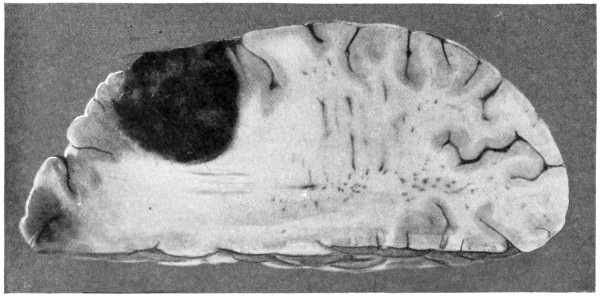

| 62. A glioma of the brain | 211 |

| 75. A large right-sided temporo-sphenoidal abscess | 256 |

| 76. To illustrate the pressure effects of a temporo-sphenoidal abscess | 257 |